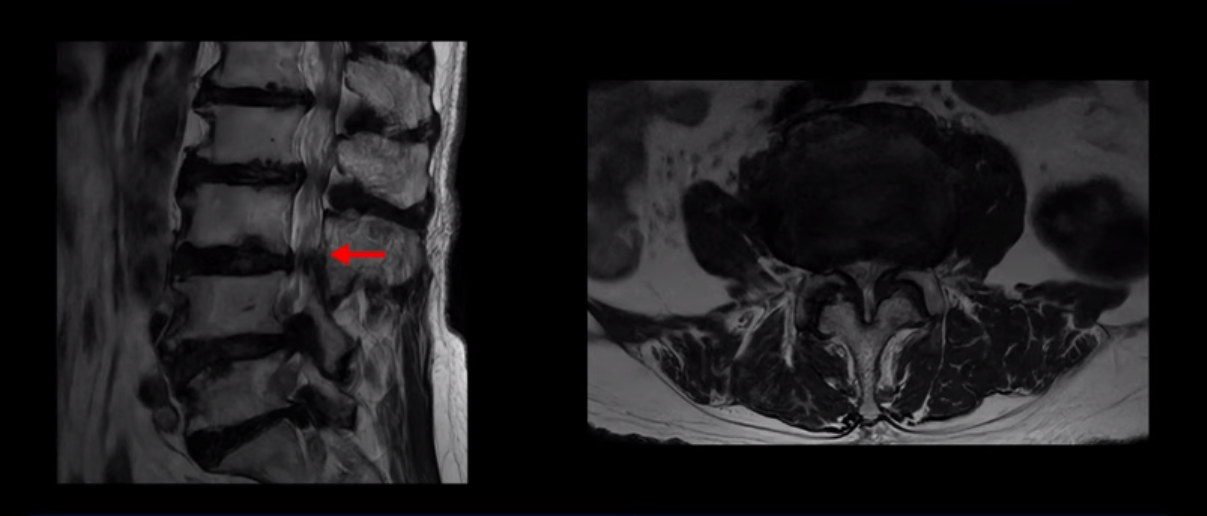

이 환자분은 MRI로 보면 허리 여러 마디가 신경이 매우 심하게 눌려 보이는 분입니다. 이분 MRI를 보면서 간단히 설명해 드린 후 어떻게 이렇게 신경이 심하게 눌린 환자분이 수술 없이 근육신경재활치료로 좋아질 수 있는지, 다리가 아파 걷지 못하는 환자가 어떻게 안 아프고 잘 걸을 수 있게 되는지, 10년 동안 괴로웠던 양 발의 시린 증상은 어떻게 사라질 수 있는지, 치료는 어떻게 하는지 자세히 설명 드리겠습니다.

MRI 보시면 (2-8) 허리의 5마디가 전부 다 심하게 퇴행되어 있습니다.

5마디 전부 다 심한 중심성 협착이 있습니다.

2번 3번,

3번 4번,

이렇게 모두 다 심하게 막히는 경우는 드문데요. 또한 오른쪽, 왼쪽 신경이 빠져나가는 추간공도 다 심하게 막혀있습니다.

오른쪽, 왼쪽 이렇게 신경 구멍들이 다 좁아지고 신경이 눌리니까 양쪽 다리가 발바닥까지 아파서 걷기 어렵고 양쪽 발이 10년 넘게 시린 겁니다. 당연히 수술해서 눌린 신경을 풀어줘야 한다고 들으셨는데요. 이런 환자분을 어떻게 수술 없이 치료할까요? 지금부터 설명해 드립니다.